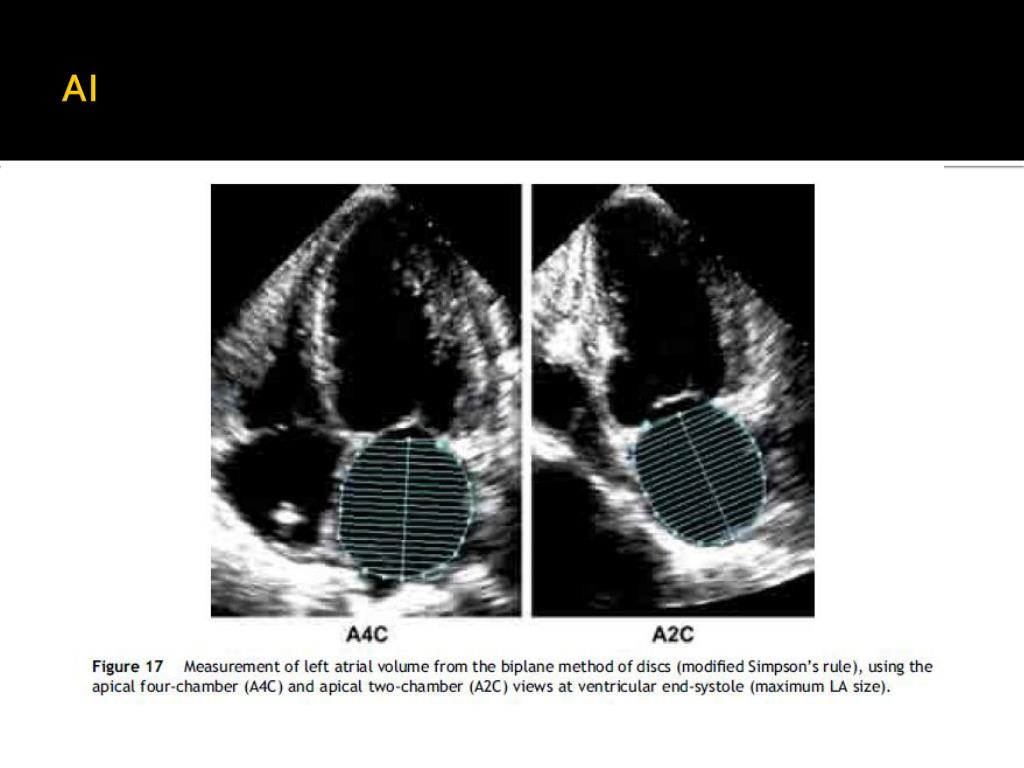

21. AI

22. AI

23. AI